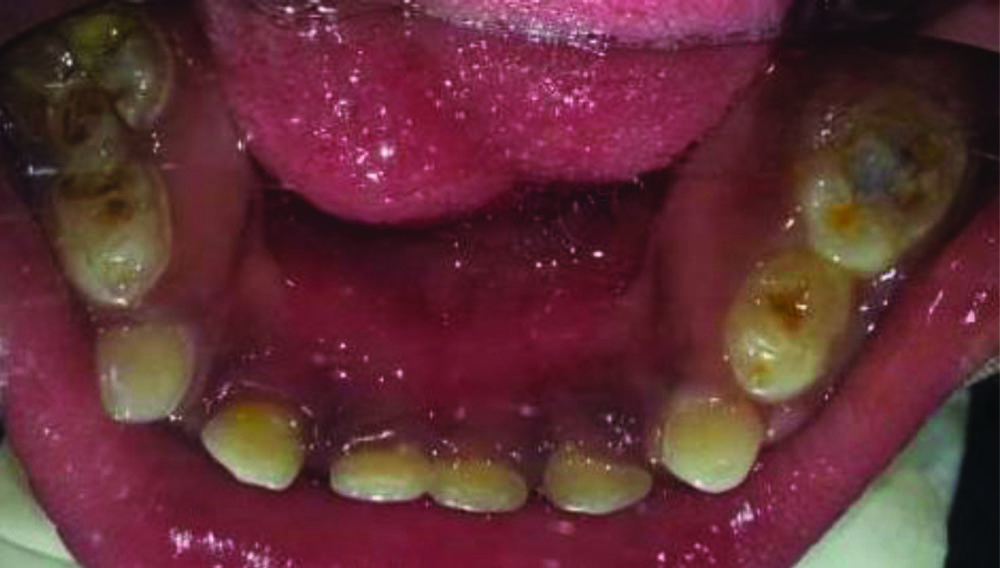

The clinical examination revealed short stature and a short neck length, an increased circumference of the head, and rotated legs. The craniofacial features included cephalomegaly, a convex profile, a flat nasal bridge, an acute nasolabial angle, an apparent large mouth, and broad lips. Intraoral findings revealed mixed dentition with dental caries in teeth 65, 74, 85, an open bite, macroglossia, and tongue thrusting with food pouching, an Ellis class III fracture in the right central incisor, along with generalised attrition. Soft tissue was normal with generalised plaque and calculus deposits [Table/Fig-1,2,3,4 and 5]. The temporomandibular joint was diagnosed as normal. Radiographic investigation was planned to assess the status of the dental pulp, but the patient was unco-operative for the investigation. The treatment was planned to proceed with caries excavation and a review of the status clinically. Informed consent was obtained from the parent prior to commencing the procedure, and medical consent was obtained from the paediatrician. Diet counselling and oral hygiene measures were taught, along with medications prescribed to relieve pain. The patient was managed by employing non invasive techniques like conditioning, desensitisation, and positive reinforcement, and good co-operation was achieved.

Photograph showing preoperative mandibular arch.